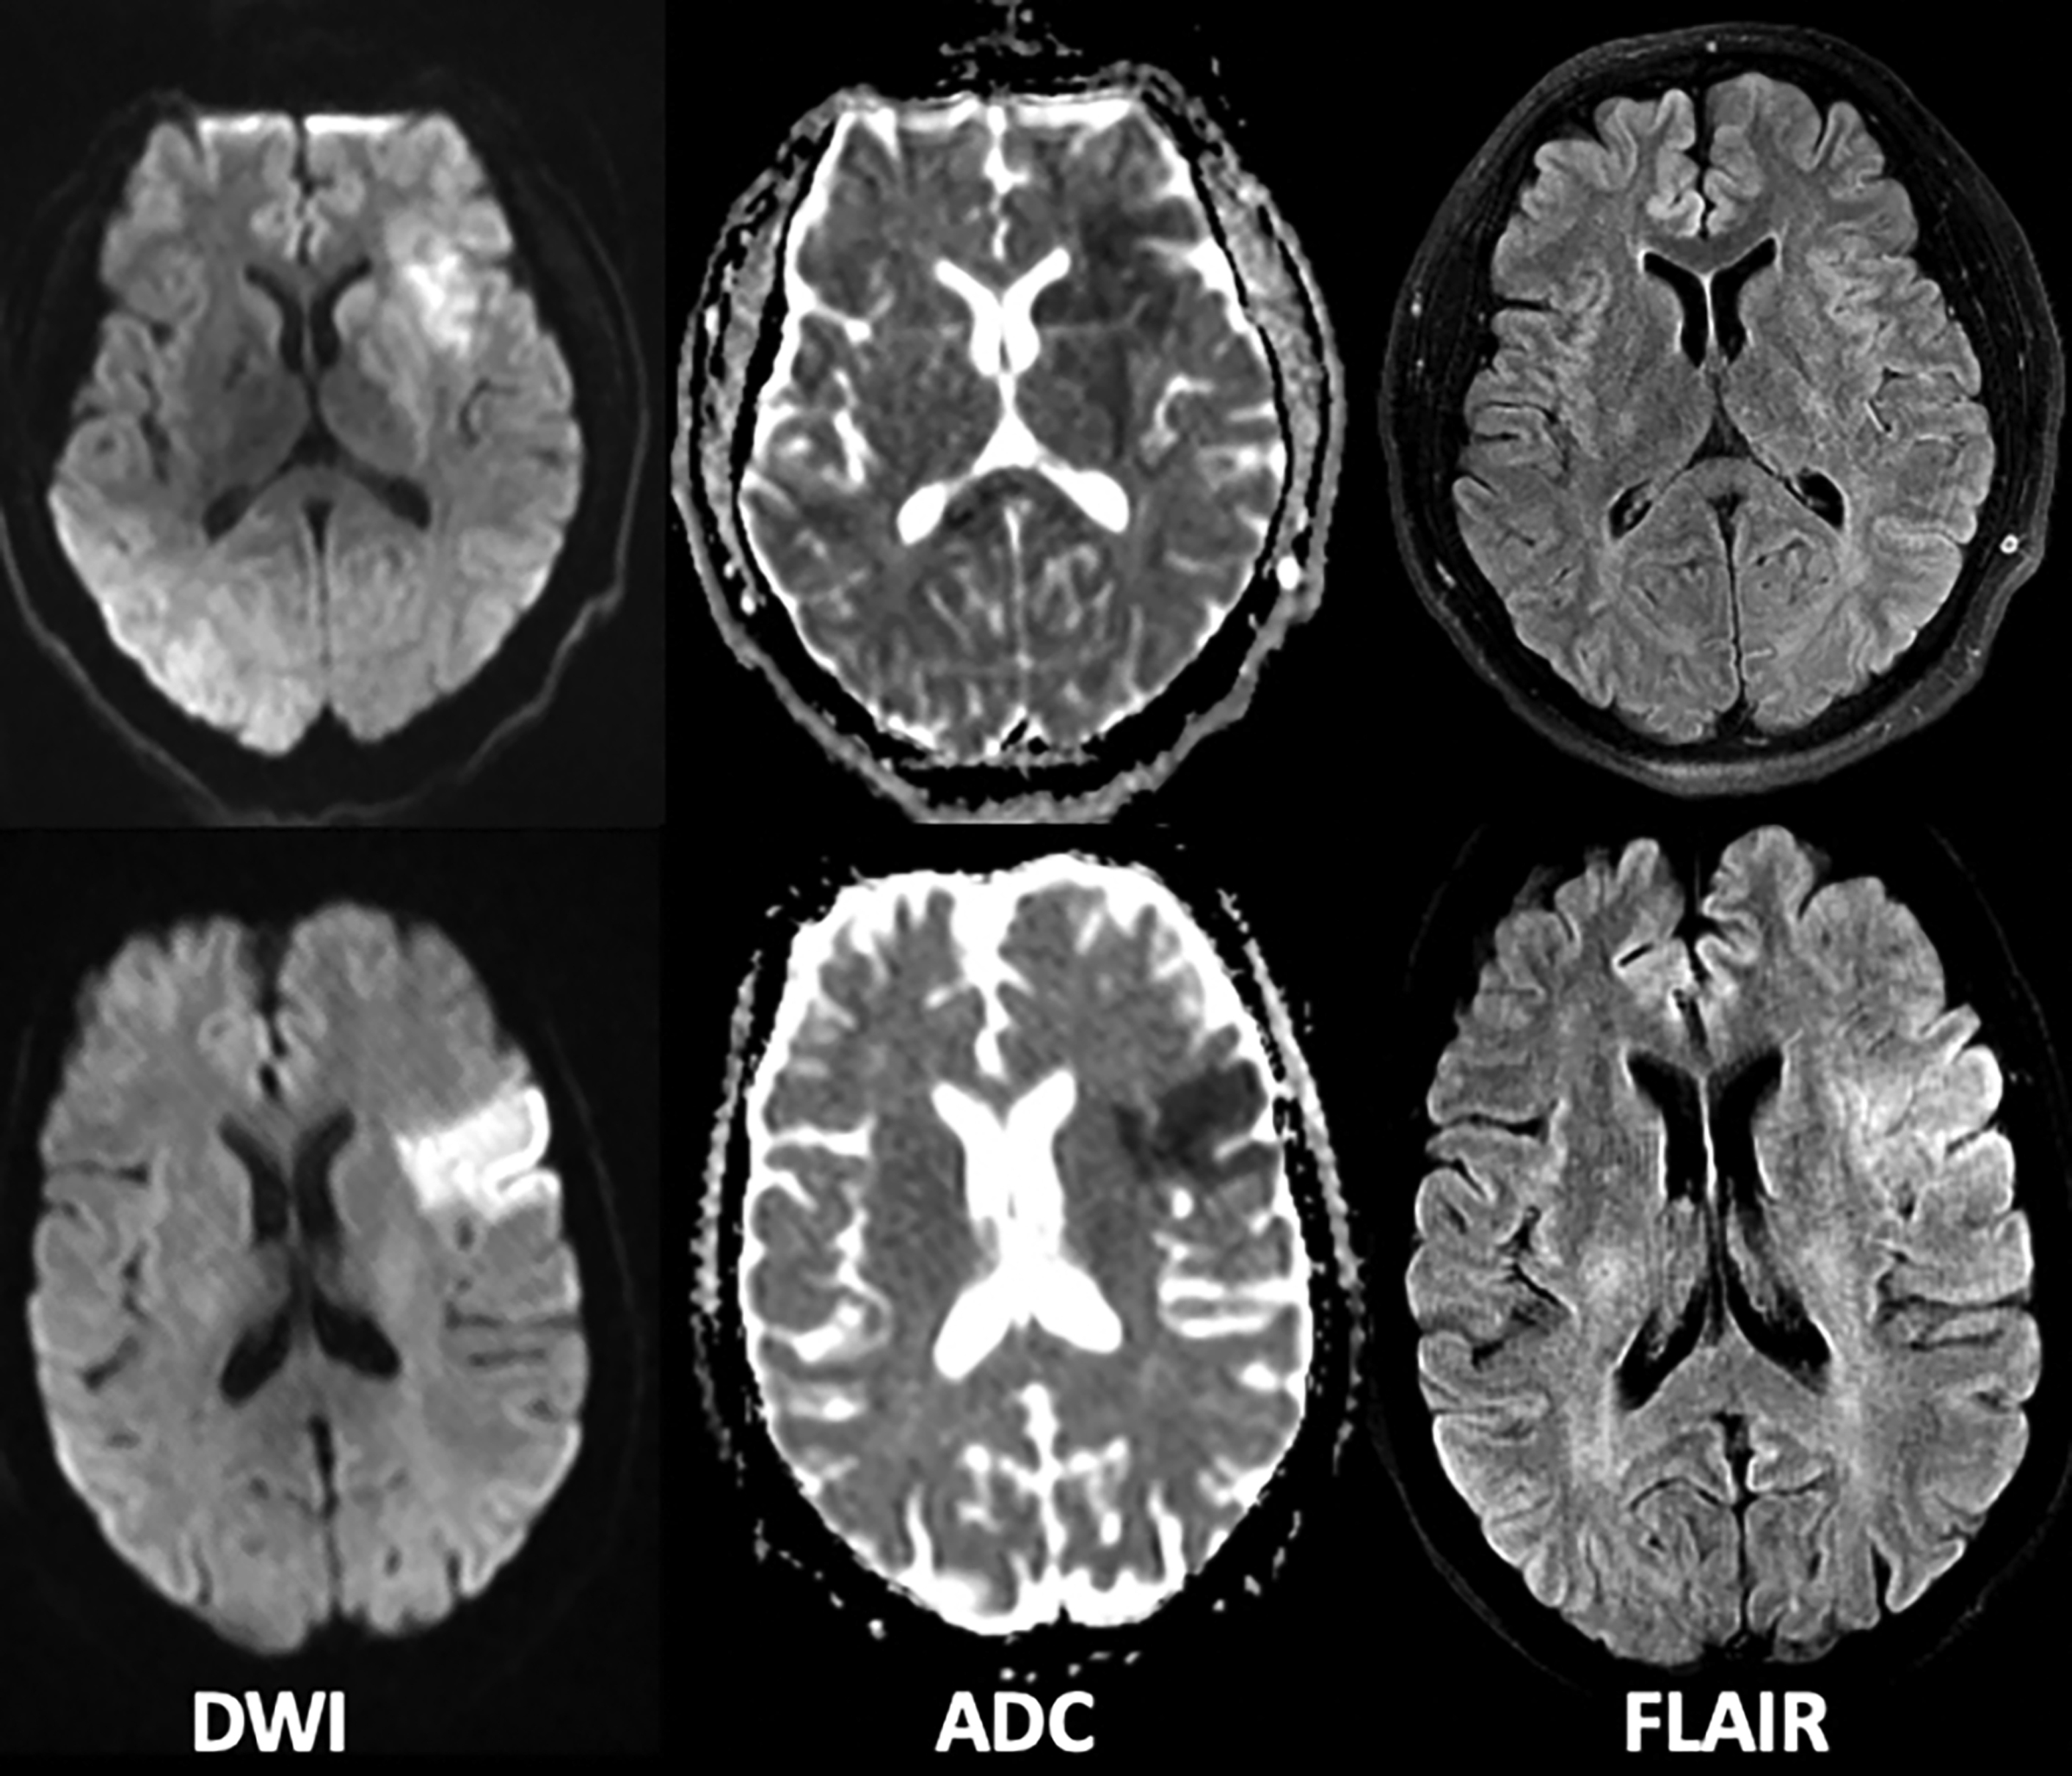

MRI findings in acute and subacute strokes. (A) During acute stroke Can You See A Past Stroke On Mri A brain ct scan (also called a cranial ct scan) can show if there is damage or bleeding in the brain. Silent strokes are small strokes that may occur in a part of the brain that doesn’t cause visible symptoms. An mri may also show certain types of stroke better or. With an old stroke, tissue scarring may appear as. Can You See A Past Stroke On Mri.